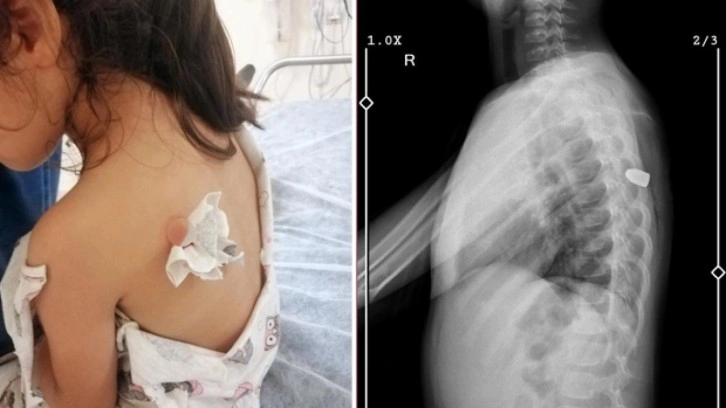

Sırtındaki kanamayı gören anne Ergün, kızını Adana Şehir Eğitim ve Araştırma Hastanesi’ne götürdü. Yapılan kontrolde Meliha Beray’ın sırtına yorgun mermi isabet ettiği anlaşıldı. Ameliyatla sırtındaki kurşun çıkarılan Meliha Beray, 2 gün yoğun bakım ünitesinde kaldıktan sonra servise alındı.

Olay anını anlatan Canan Ergün, "Oyun alanında birden bağırdı ve olduğu yere yığıldı. Bir şey battığını düşündük. Hatta kızım da böcek ısırdığını zannetmiş, bu şekilde söyledi. Hastaneye geldiğimizde ultrasona alındı ve kurşun isabet ettiğini öğrendik. Bu duruma inanamadık. Silah sesi duymamıştık, nereden geldiğini de anlayamadık. Kurşun çıkarıldı, tedavisi devam ediyor. Hayati tehlikesi yok çok şükür" diye konuştu.